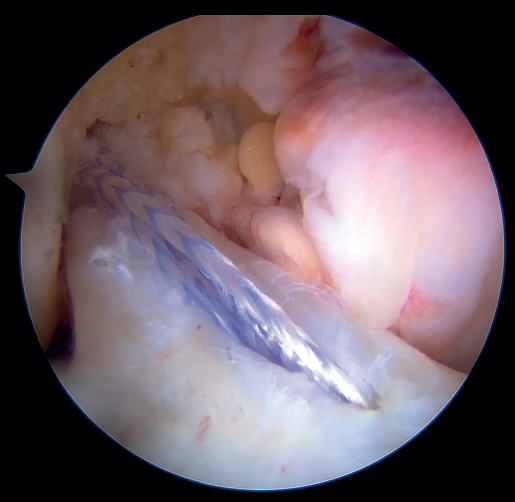

The next step is to remove the femoral retriever thread through the cannula of the anteromedial portal, loading it with the traction and flipping sutures, but not with the high strength tape. By pulling on the retriever thread, the ACL RepairTightRope® sutures will pass through the femoral tunnel (Figure 9), exiting through the skin. Using the lift sutures, the button is then likewise advanced through the tunnel until it is flipped over the lateral femoral cortex (which can be checked by pulling firmly on the high strength tape, which still exits through the cannula). At this point, all that remains is to pull alternately on both loop traction sutures to shorten the loop and reduce the stump of the ACL until contact is made with its native footprint.

As the last step of the procedure, the high strength tape connected to the cortical button is retrieved through the anteromedial portal, where the tibial tunnel retriever thread is located. By loading the tape onto the thread and pulling on it, the tape now lies in front of the repaired ligament and exits through the anteromedial cortex of the tibia, where it is fixed with the knee fully extended with a tenodesis implant (SwiveLock®, HealiCoil®). After completing the procedure, it is advisable to check the tension of the ligament and the InternalBrace®, as well as the absence of impingements and limitations in mobility of the knee (Figure 10).